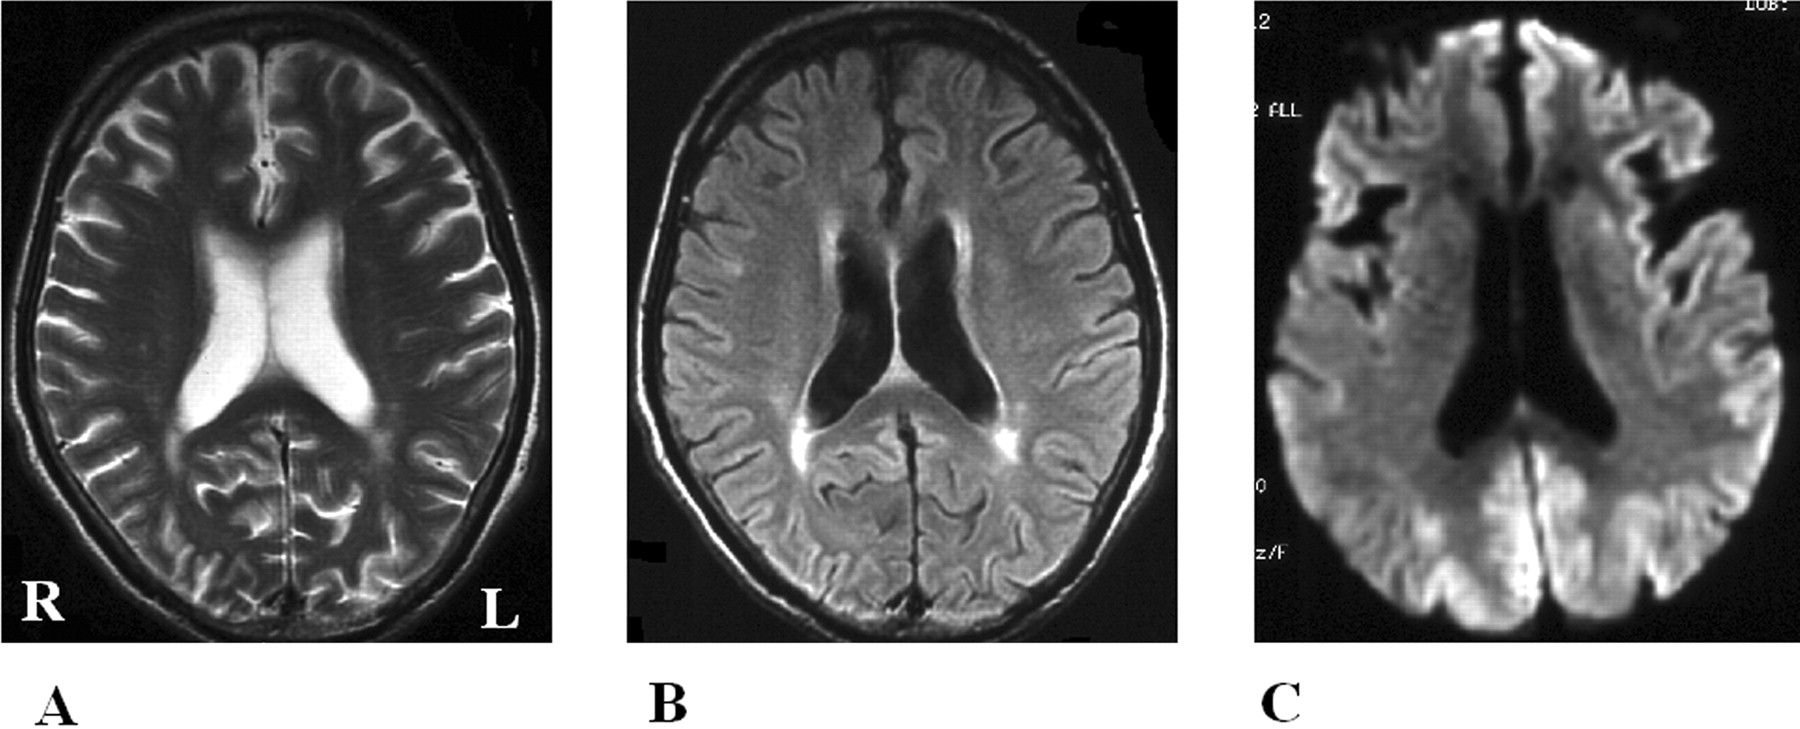

酒后驾驶是在26日检查库贾氏症患者发病后3到25周平均持续时间为10.7周。24库贾氏症患者表现出高强度脑损伤的驾车考试。两个观察者,醉酒驾车的库贾氏症诊断的敏感性为92.3%。interobserver协议率为100%。3例(12.5%)显示只在尾状头和硬膜损伤,10例(41.7%)患者显示线性损伤只有在大脑皮层,和11例(45.8%)患者显示病变基底神经节和大脑皮层(图1)。其中,只有三个病人(12.5%)显示,丘脑病变。没有病人显示高强度在小脑病变。高强度损伤在驾车之前出现脑萎缩。病变包括纹状体初并不总是对称的但是后来对称(图2),尽管对称的纹状体病变是众所周知的在库贾氏症。11在某些情况下,高强度损伤与连续驾车并不总是进展的疾病,而有时信号强度降低了疾病进展的一些病变。在某些情况下,皮质高信号强度不同,解剖分布(图3)。在终端阶段与深刻的脑萎缩,高强度损伤变得不清楚。T2I DWI-examined 26日在23日检查病人,但T2I扫描被排除在外,因为低质量由于运动构件。一位观察家认为11 22患者阳性(50.0%),而另一个观察者认为8阳性(36.4%)。interobserver协议率为68.2%,低于酒后驾车(p< 0.005)。在这两个观察者,醉酒驾车是比T2I更敏感(p一个观察者,< 0.005p另一个观察者p < 0.0005)。天赋是17 26患者的检查。一位观察家认为10 17例阳性(58.8%),和另一个观察者认为7是积极的(41.2%)。interobserver协议率为82.4%,也低于酒后驾车(p< 0.05)。醉酒驾车是比天赋更敏感(p一个观察者,< 0.01p另一个观察者p < 0.0005)。我们在图4一个例子中,只有醉酒驾车可以检测高强度异常病变。

图2。按时间顺序的改变的纹状体和皮质病变。零星的克雅氏病(CJD)显示基底神经节的进展信号变化不对称对称(B) (A)。(A)和(B)之间的间隔是2个月。的家族与V180I突变库贾氏症显示大脑皮层的进展和尾状核头信号变化不对称(C)对称(D)。(C)和(D)之间的间隔是4个月。